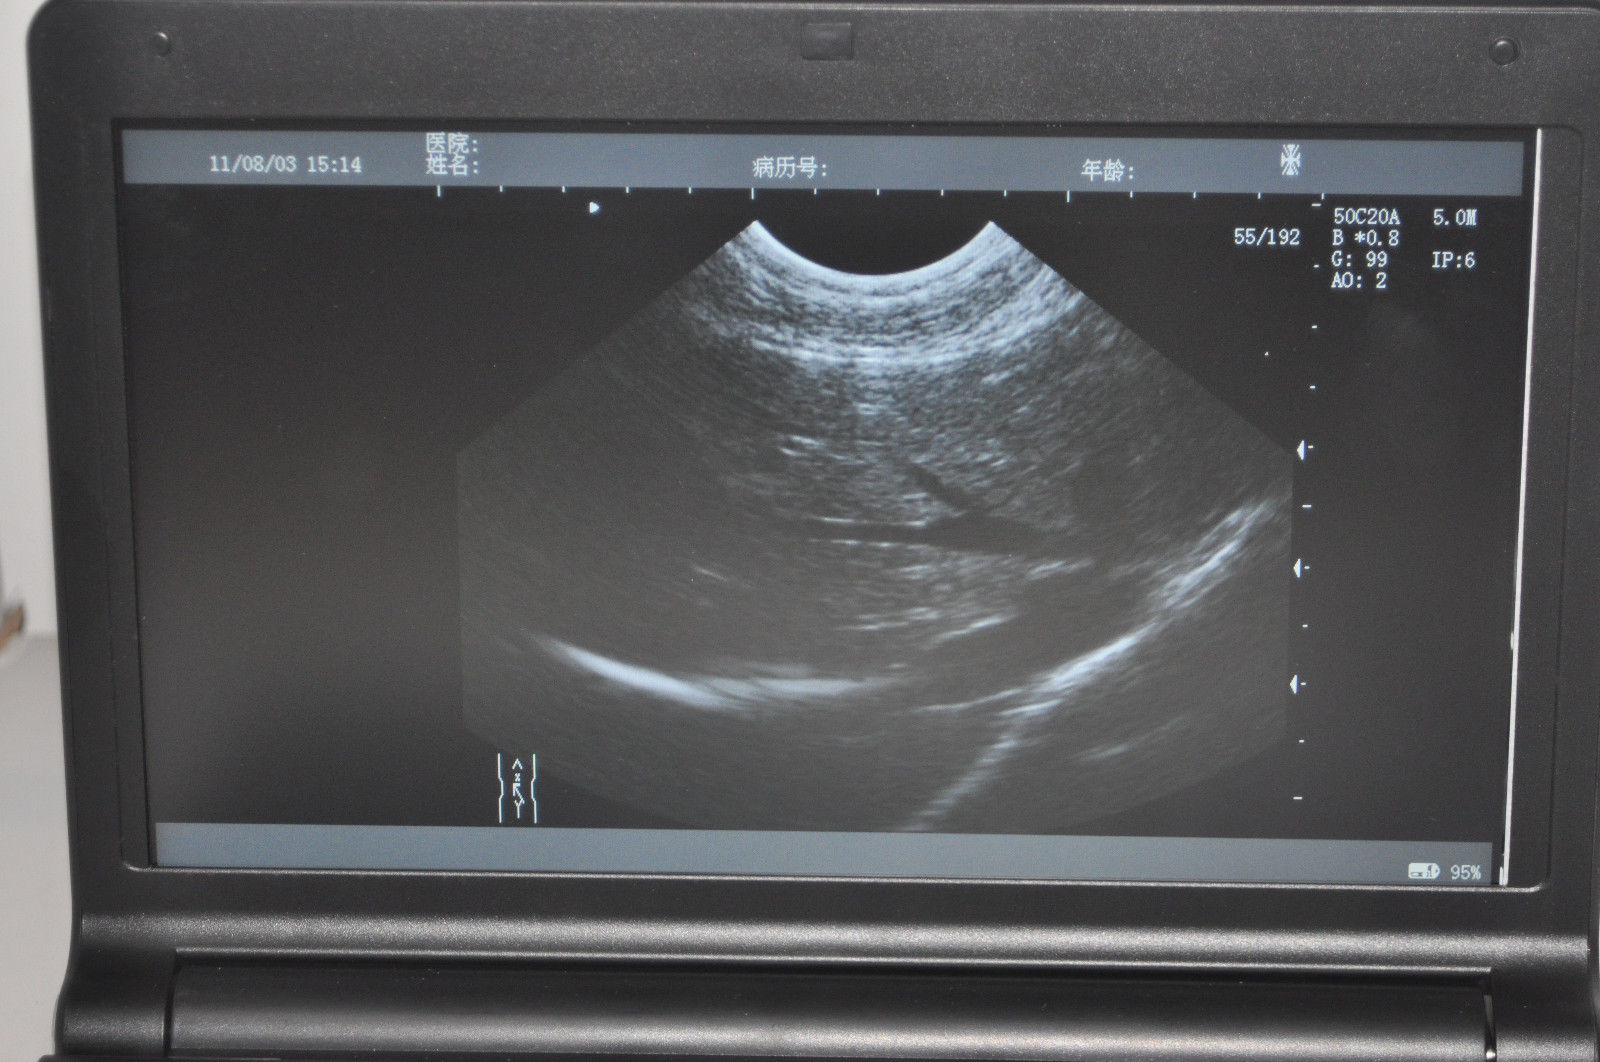

Impressive Imaging Technology

The CE Digital Laptop Ultrasound Machine offers outstanding imaging capabilities that are essential for modern diagnostic practices. It features a 6.5MHz Transvaginal probe that provides high-resolution images, enabling healthcare professionals to visualize internal structures with great clarity. This machine is designed to help in various examinations, ensuring better accuracy and improved patient care.

The CE Digital Laptop Ultrasound Machine enhances user experience with its intuitive interface and advanced functionality. It supports 3D imaging, allowing healthcare providers to obtain more detailed views of the anatomy being examined. This capability is invaluable for procedures such as gynecological assessments, as it provides a comprehensive perspective that traditional ultrasound machines cannot offer.